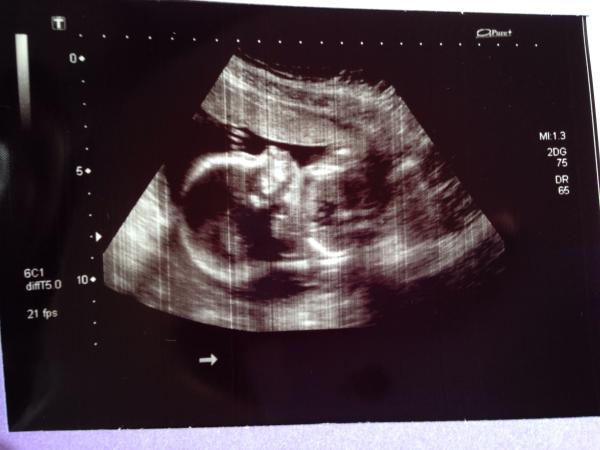

Wow, that has to be the clearest looking scan pic I've ever seen, MissingCaffeine. Is that just regular 2d?

Foodie it's just a regular scan. Our last scan was really clear too at 12 weeks so maybe it's just a very good machine - as it was on the same scanner. It's actually clearer than that picture, as I've lost quality in taking photo of a photo on a rubbish phone camera.

It's amazing. Congratulations!